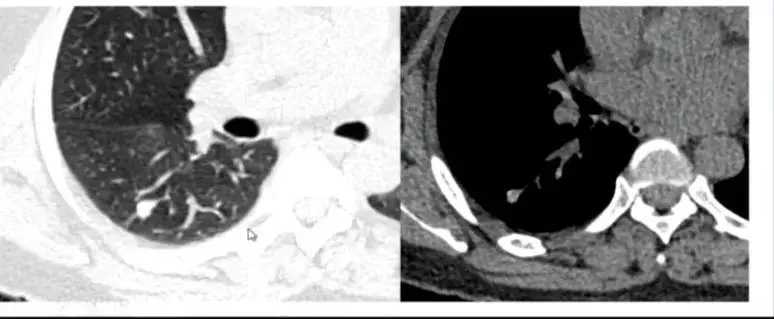

11. 结核厚壁空洞

图15

图15 结核厚壁空洞,结核处于活动期的典型表现,可结合实验室检查。